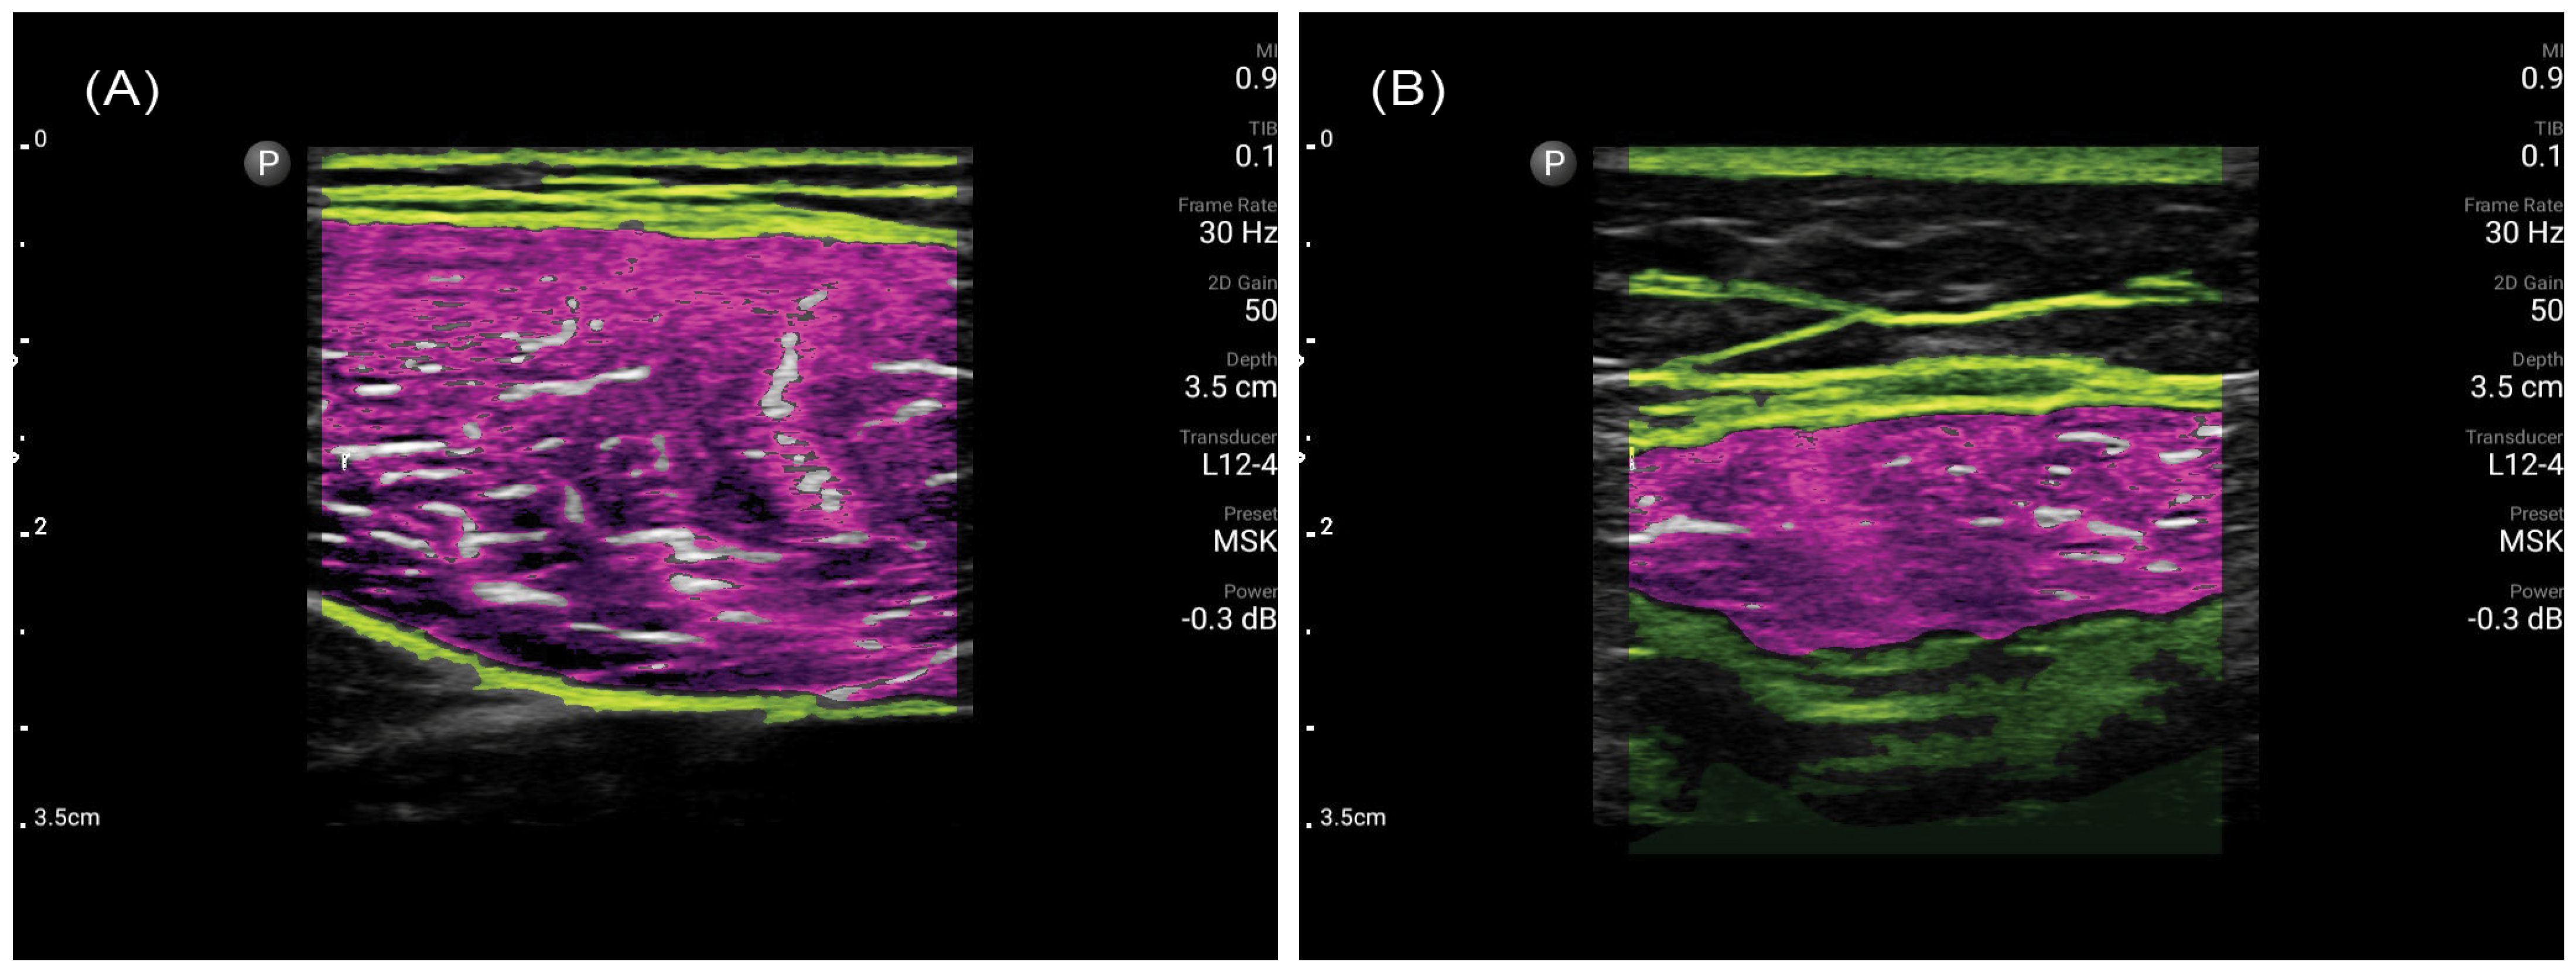

2.2. Muscle Ultrasonography Procedure

4. Discussion